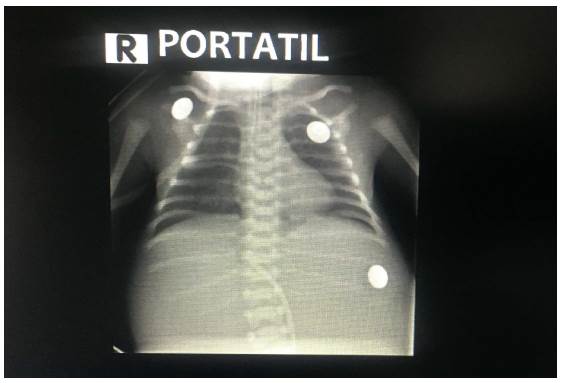

Hacia la semana 33 de gestación, ingresa nuevamente la paciente al servicio de urgencias de Ginecología y Obstetricia, con amniorrea evidente y en trabajo de parto en fase latente. Se realiza cesárea de urgencias por estado fetal no tranquilizador según reporte de monitoría fetal electrónica. Se recibe recién nacido femenino Ballard para 33 semanas, con peso de 1.780 g considerado adecuado para edad gestacional, con adaptación conducida y posterior falla ventilatoria, requiriendo intubación orotraqueal. En el examen físico se evidenció implantación baja de las orejas, arteria umbilical única, abdomen distendido, ano imperforado con fístula recto vestibular y genitales femeninos externos normoconfigurados. Es trasladada a unidad de cuidados intensivos neonatales, en donde se realiza radiografía de tórax y abdomen (Figura 5), la cual muestra arcos costales derechos fusionados, hemivértebras y ausencia de gas en cámara gástrica, considerando una atresia esofágica tipo 1. Dados los antecedentes prenatales, los hallazgos clínicos e imagenoló-gicos, se considera una asociación VACTERL y se decide completar el estudio de posibles anormalidades asociadas, realizando ecocardiograma, ecografía transfontanelar, ecografía renal y vías urinarias, todas reportadas normal. Fue llevada a su primera cirugía a las 48 horas de vida, donde se le realizó gastrostomía, colostomía y resección de membrana duodenal. A los 11 días de vida se realizó inicio del estímulo enteral trófico por gastrostomía. En segundo tiempo quirúrgico, 34 días después, se realizó toracotomía derecha y anastomosis término terminal esofágica.